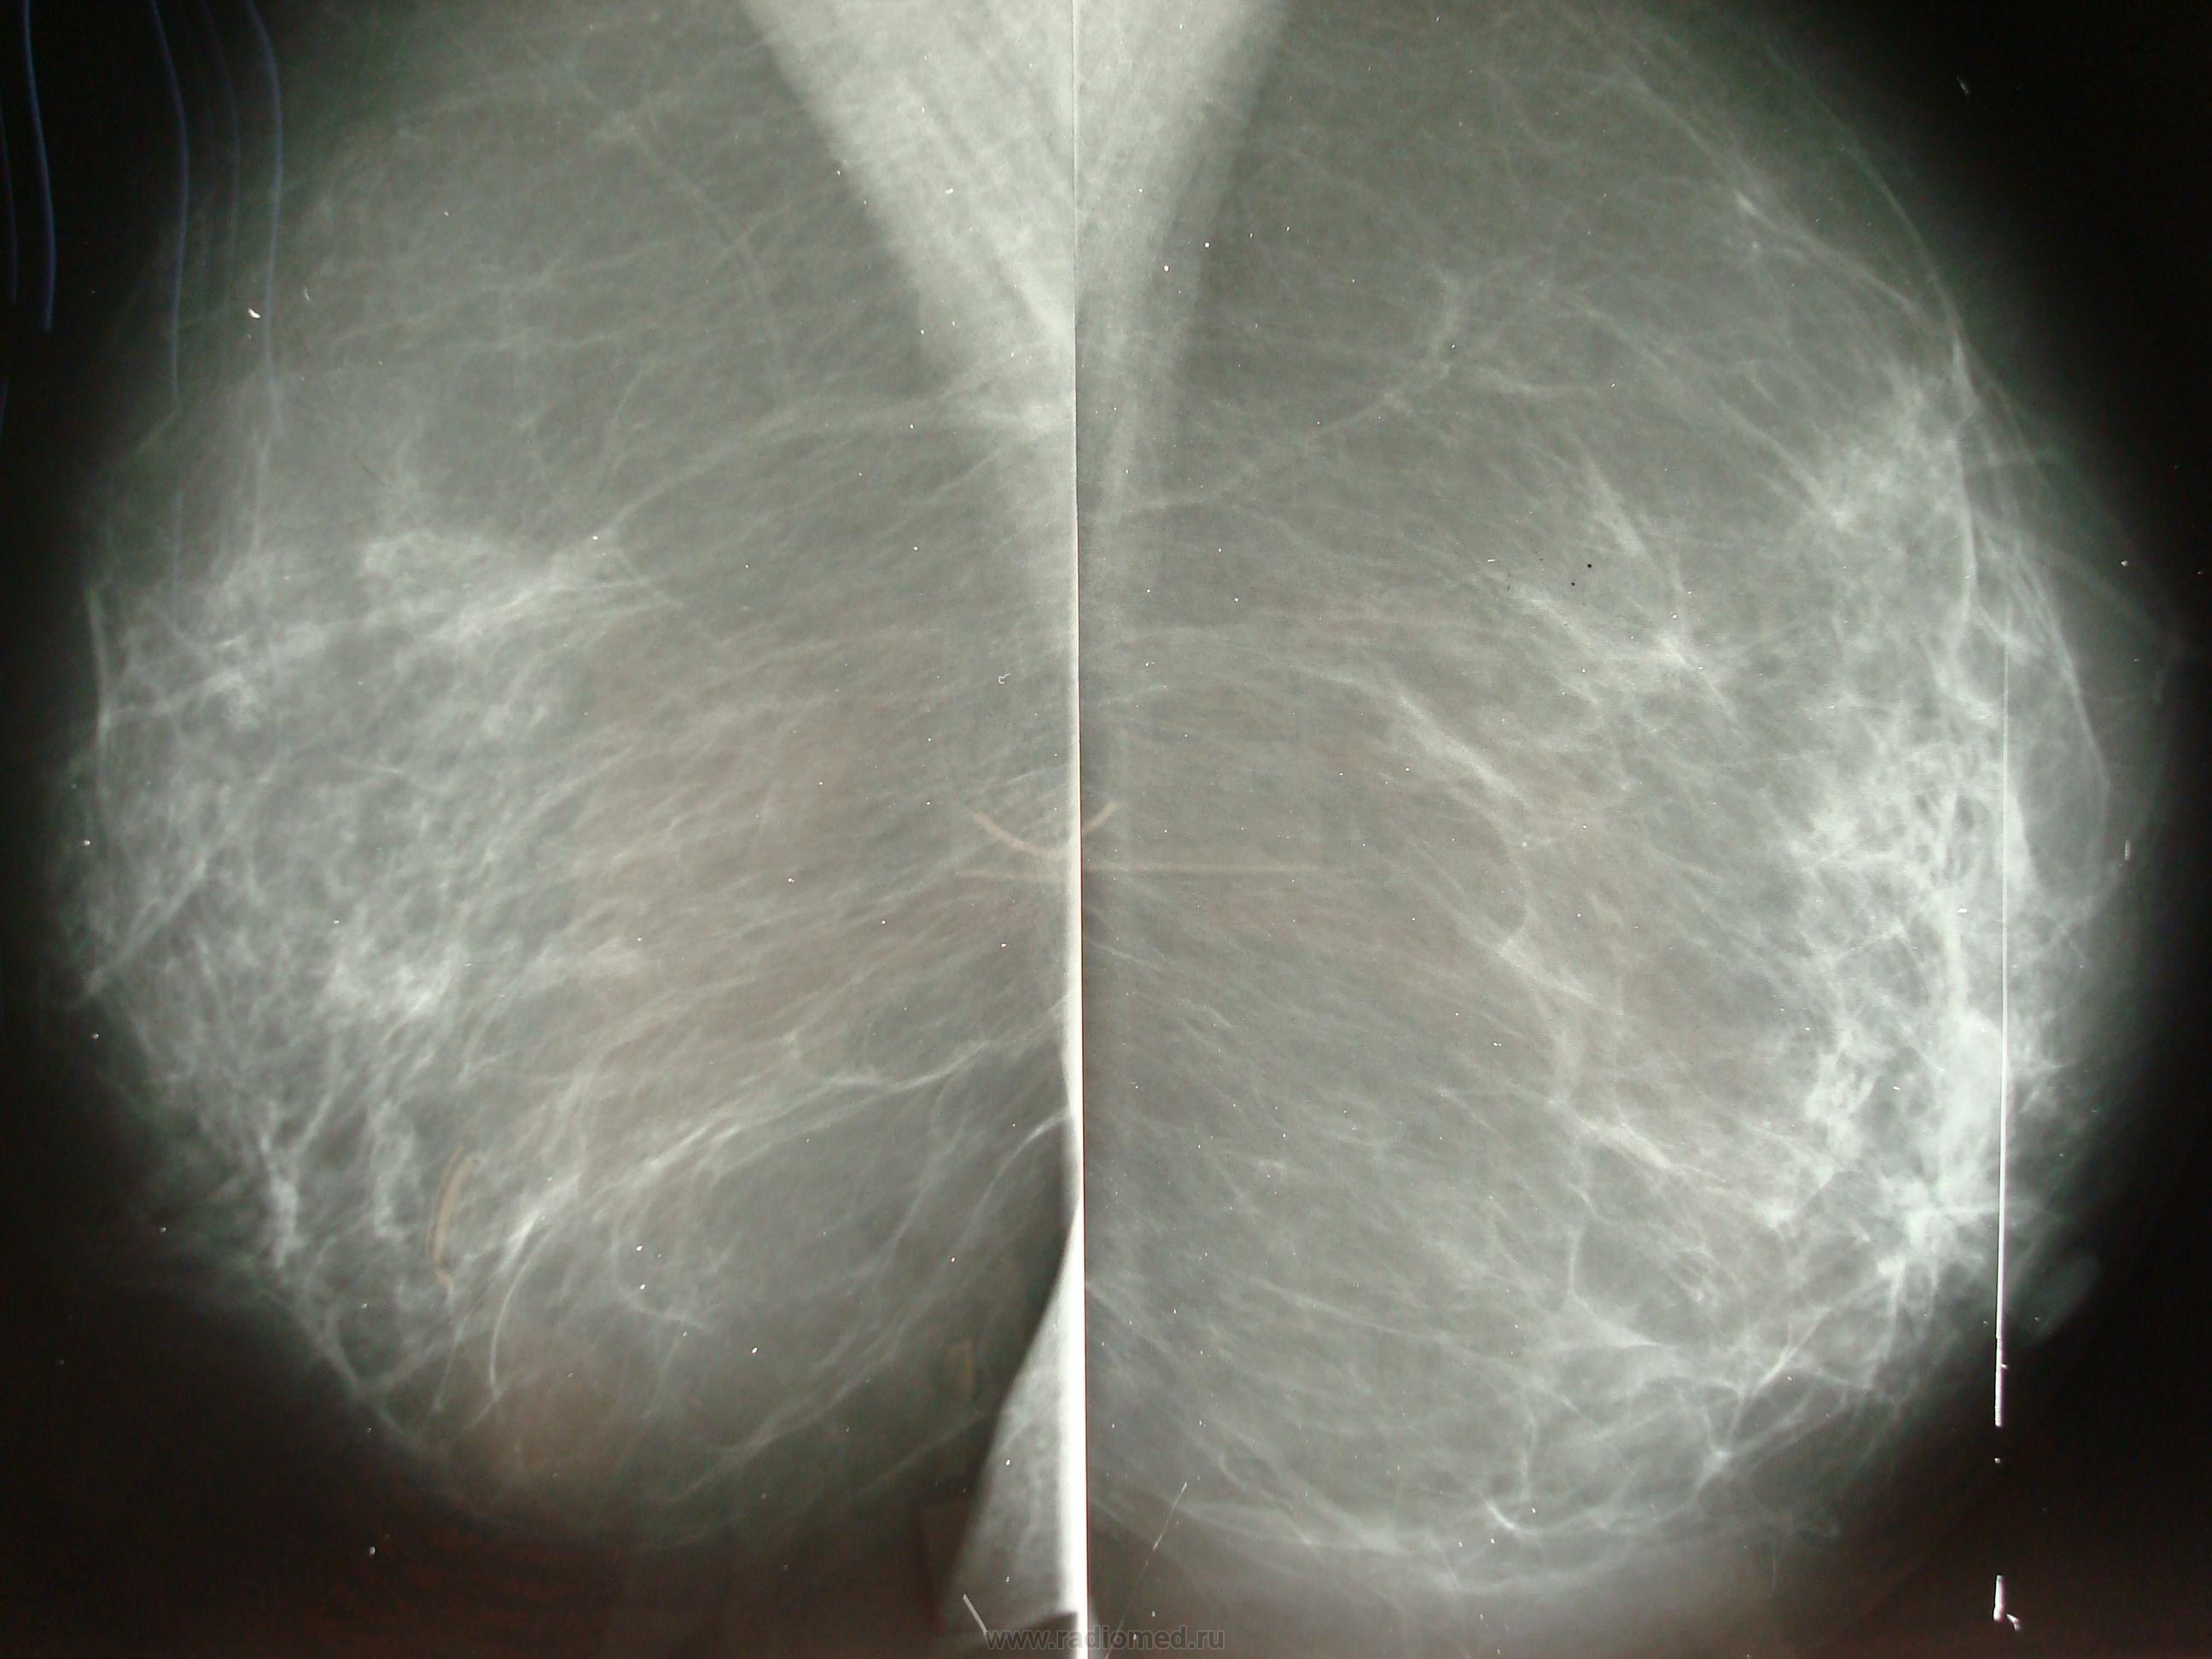

Фиброаденома молочной железы - доброкачественное образование, которое часто встречается у женщин. Оно может быть обнаружено при помощи различных методов диагностики, включая маммографию. Ниже представлены фотографии, помогающие понять, как выглядит данное заболевание.

Маммограмма железистая ткань

Фиброзно-кистозная мастопатия молочных на маммографии

Маммография и ее роль в диагностике фиброаденомы молочной железы

Маммография - это рентгенологическое исследование молочных желез. Оно позволяет выявить различные изменения в тканях, включая фиброаденому. На маммограммах можно увидеть структурные особенности опухоли и отследить ее динамику во времени.